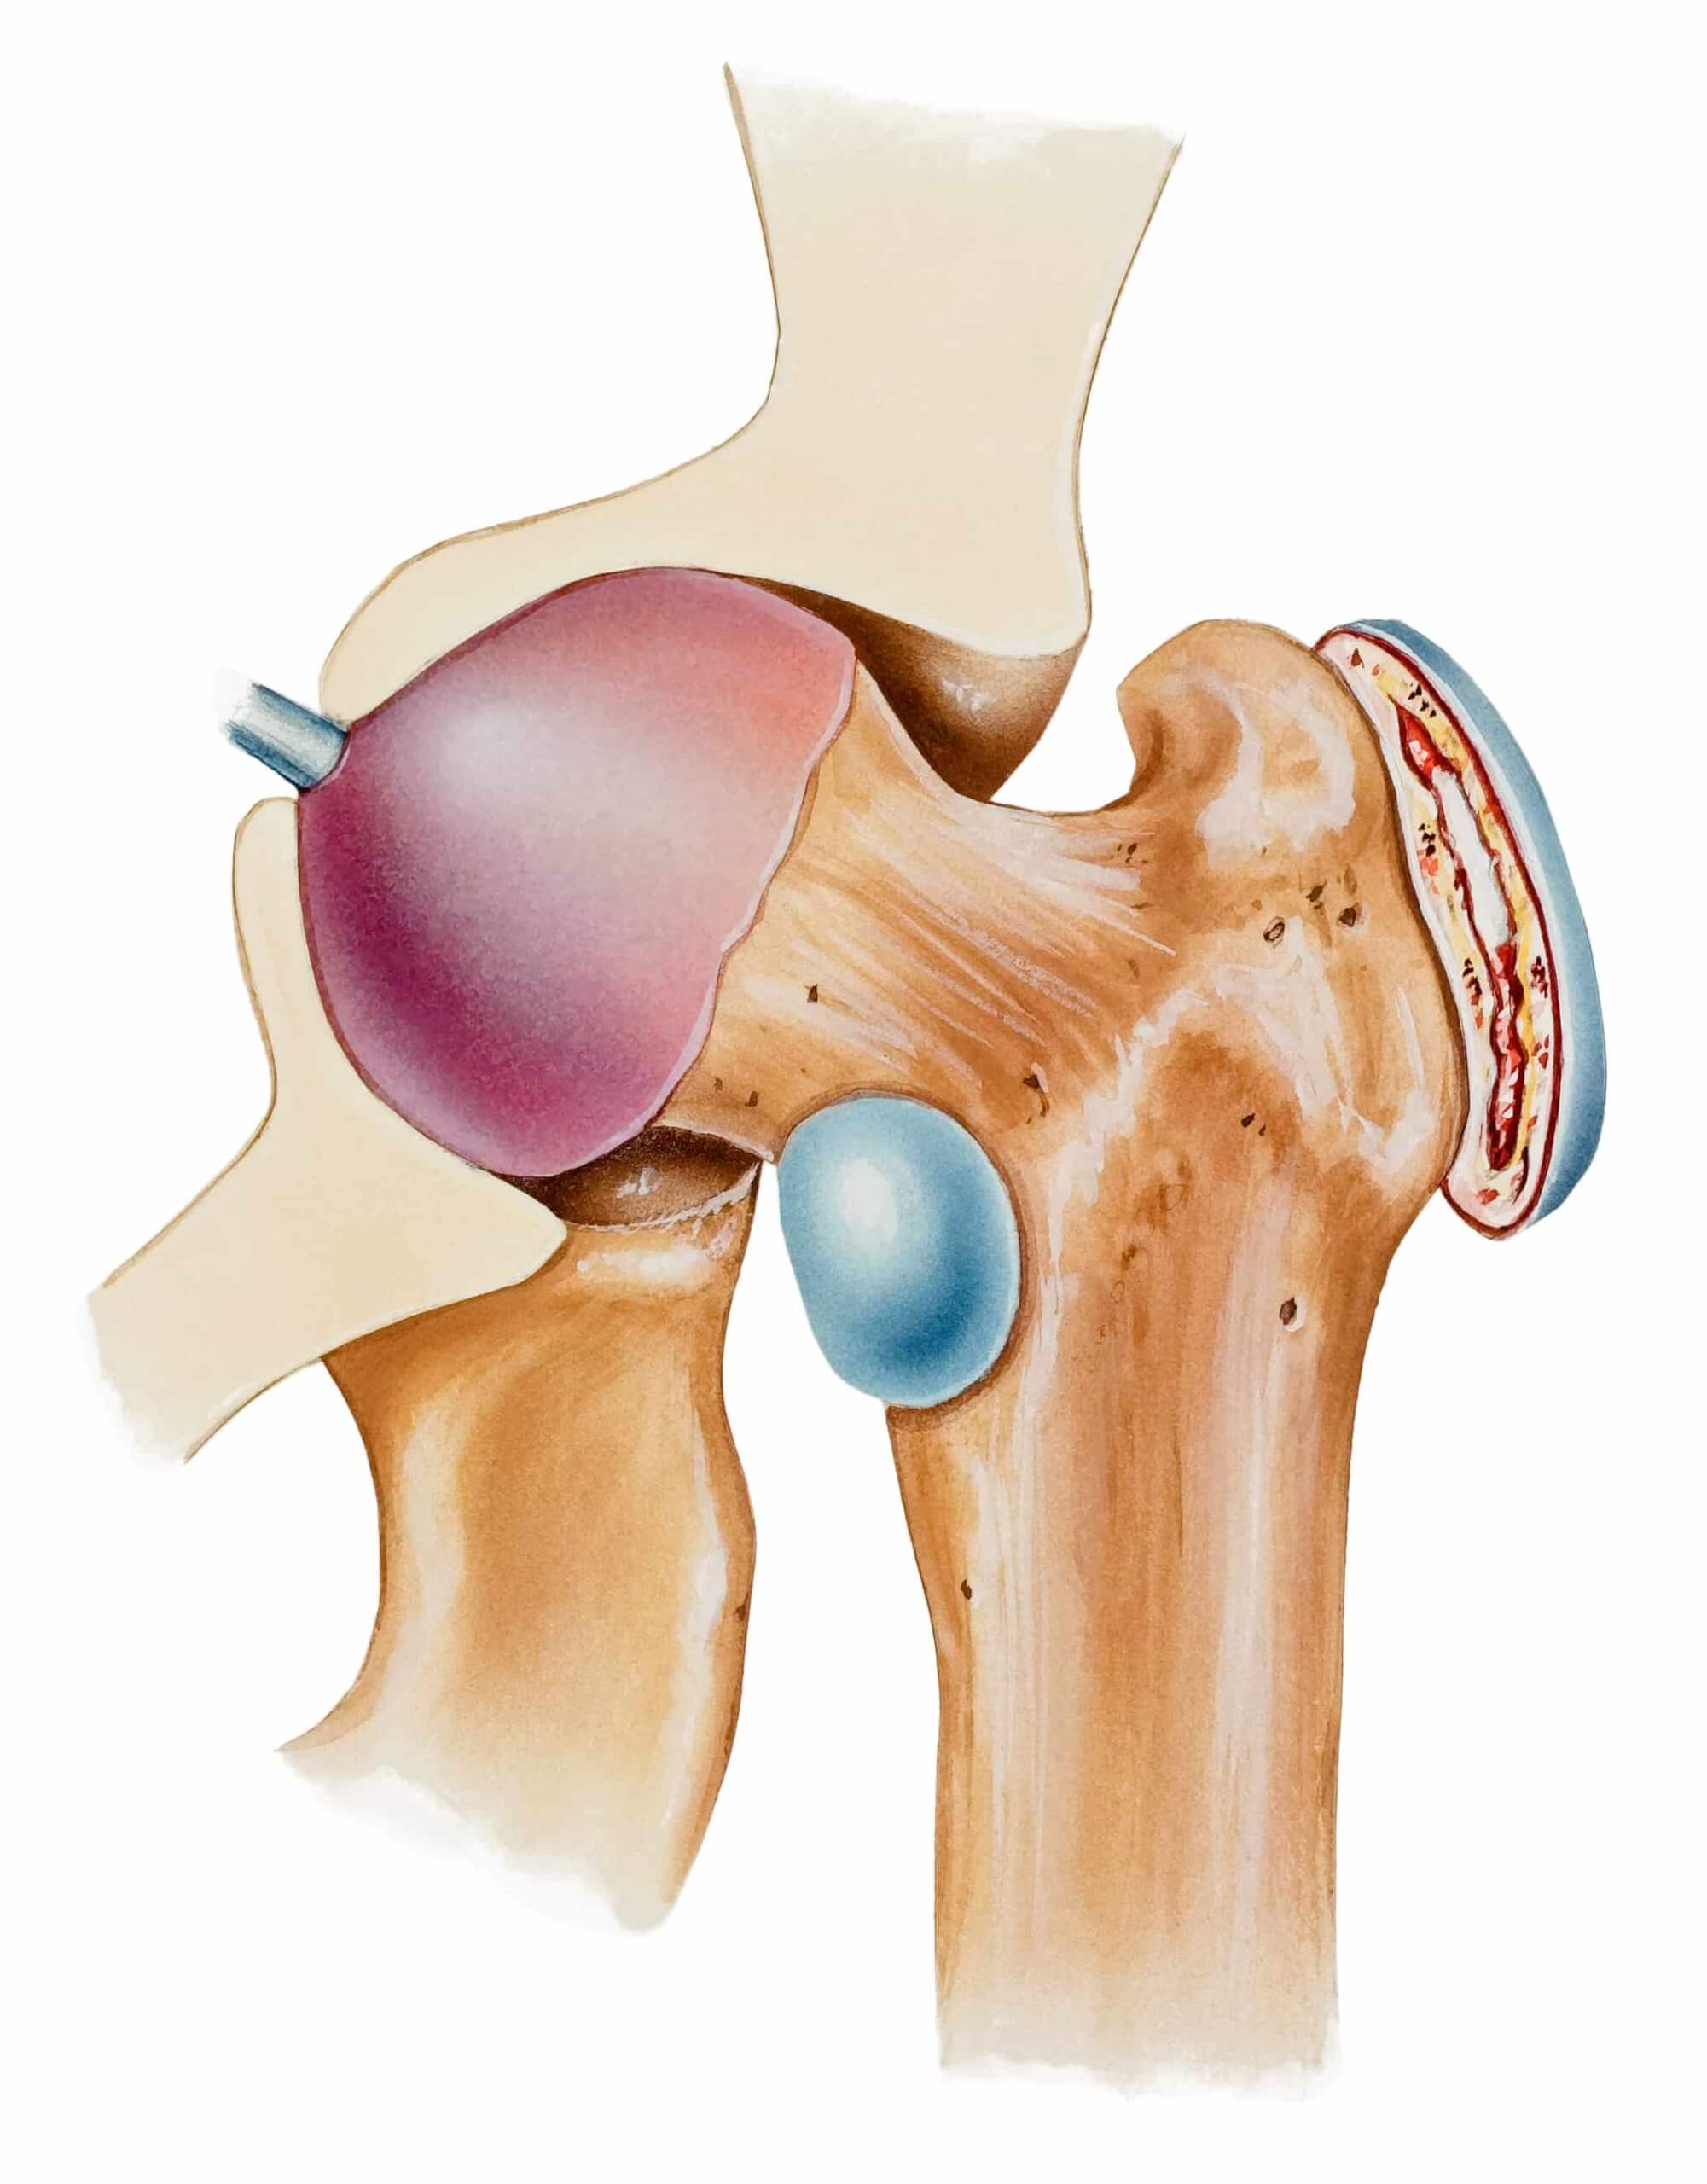

Burzitis kolka je vnetje burze oz. sluznika, manjših žepkov, ki so locirani med kito in kostjo. Burze zmanjšujejo trenje med kitami, mišicami in preostalimi sklepnimi strukturami ter izboljšujejo sklepno mehaniko, gibanje posledično teče bolj gladko.

Burzitis kolka imenujemo tudi trohanterni burzitis, kolčna burza se nahaja na zunanji strani kolčnega sklepa, med velikim trohantromom ter iliotibialnim traktom.

Kolčni burzitis je pogostejši s starostjo in zaradi večjega kota med stegnenico ter navpično linijo pogosteje prizadene žensko populacijo vzrok nastanka burzitisa v kolku ni znan, dejavnik tveganja predstavljajo kronične fizične preobremenitve npr. tek in travmatske poškodbe kolčnega sklepa.

Akutna oblika burzitisa v kolku se običajno pojavi po visokem naporu ali po specifičnih obremenitvah. Kolčna burza se lahko vname tudi zaradi mišičnih neravnovesij, togih mišičnih skupin in/ali vezi, nepravilne biomehanike hoje in/ali slabše stabilnosti medenice in trupa. Kronični burzitis kolka, ki traja več mesecev se običajno navezuje na predhodne, ponavljajoče se travmatske poškodbe kolka.

Vnetje kolčne burze izzove močno bolečino, ki se navidezno pojavi od nikoder in se sprva pojavlja le med tekom, hojo po stopnicah navzgor ali pri aktivnostih, ki vključujejo intenzivno gibanje v kolku. Bolečina se iz kolčnega sklepa lahko širi po nogi navzdol vse do nivoja kolena. Bolečinska simptomatika se običajno pojavi postopno in lahko postane kronična. S stopnjevanjem simptomov, se zmanjša gibljivost kolka, bolečina pa postane prisotna tudi pri hoji po ravni podlagi, pri dolgotrajnem sedenju in kronično v mirovanju.